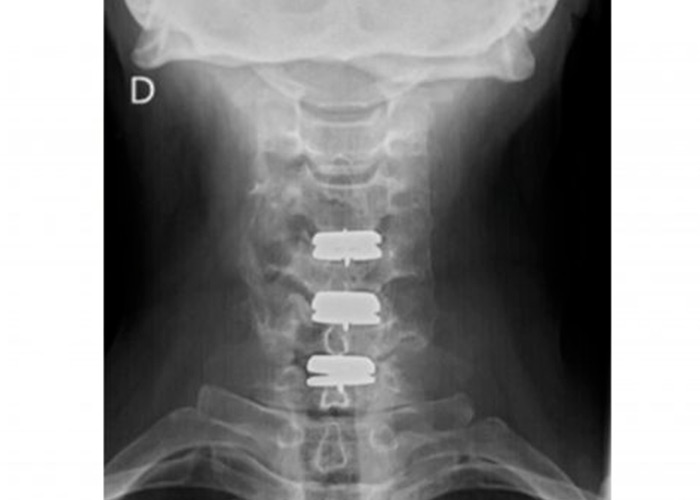

protesis-cervical-movil-instituto-cac

Postoperatorio

En menos de 5 horas el paciente se recupera de la operación. Asimismo, la movilización del cuello comienza desde el primer momento y no se precisa collarín ni otros inmovilizadores.

Por último, el paciente recibe el alta hospitalaria al día siguiente de la operación.